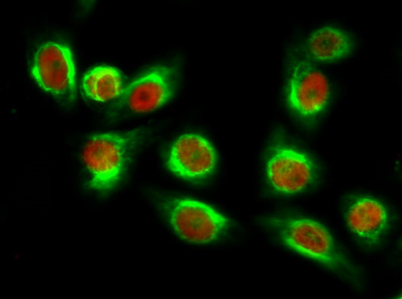

ÕŠ«õ┐ĪńöĄĶäæń½»ÕÆ©Ķ»ó

Õģ│µ│©ÕŠ«õ┐ĪÕģ¼õ╝ŚÕÅĘ

ÕŠ«õ┐Īµē½õĖƵē½Ķ┐×Õ┐ÖÕÆ©Ķ»ó

ÕŠ«õ┐Īµē½õĖƵē½Ķ┐×Õ┐ÖÕÆ©Ķ»ó